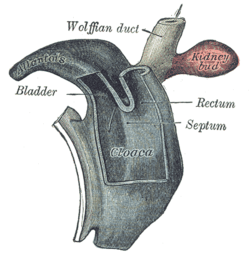

Tail end of human embryo from fifteen to eighteen days old. Cloaca of human embryo from twenty-five to twenty-seven days old.

Cloaca of human embryo from twenty-five to twenty-seven days old. Tail end of human embryo twenty-five to twenty-nine days old.

- The human allantois is an endodermal evagination of the developing hindgut which becomes surrounded by the mesodermal connecting stalk known as the body-stalk. The body-stalk forms the umbilical vasculature. In other words, the allantois is a caudal diverticulum (out-pouching) of the yolk-sac. It is externally continuous with the proctodeum and internally continuous with the cloaca. The embryonic allantois becomes the fetal urachus which connects the fetal bladder (developed from cloaca) to the yolk sac. The urachus removes nitrogenous waste from the fetal bladder.[3] The allantois is vestigial and may regress, yet the homologous blood vessels persist as the umbilical arteries and veins connecting the embryo with the placenta.[4]

During the third week of development, the allantois protrudes into the area of the urogenital sinus. Between the 5th and 7th week of development, the allantois will become the urachus, a duct between the bladder and the yolk sac. A patent allantois can result in urachal cyst.